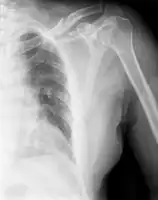

Clavicle fracture -

The basic method to check for a clavicle fracture is by an X-ray of the clavicle to determine the fracture type and extent of injury. In former times, X-rays were taken of both clavicle bones for comparison purposes. Due to the curved shape in a tilted plane X-rays are typically oriented with ~15° upwards facing tilt from the front. In more severe cases, a computerized tomography (CT) or magnetic resonance imaging (MRI) scan is taken. However, the standard method of diagnosis through ultrasound imaging performed in the emergency room may be equally accurate in children.[6]